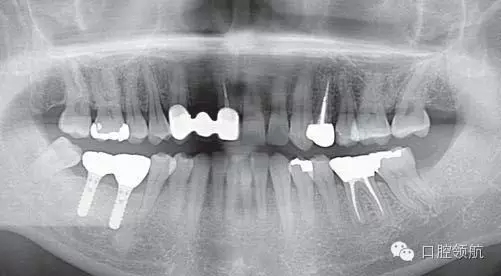

1周后(左下第六顆牙) 的牙動(dòng)度值是:+2∕+2; 7 :-2∕-2,6周后(左下第六顆牙) 的牙動(dòng)度值是:-1∕0; 7 :-3∕-3,然后安裝調(diào)改后的上部修復(fù)體(圖5、圖6)。

圖5 最終上部結(jié)構(gòu)安裝后6個(gè)月的曲面斷層片。